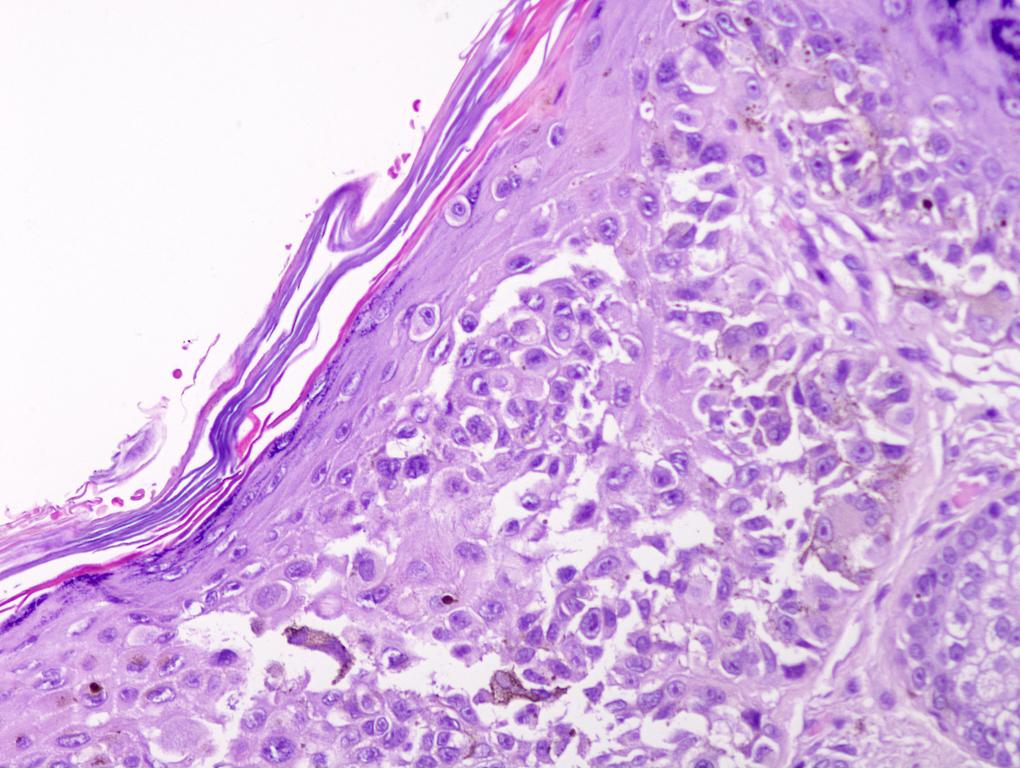

Pathology Outlines Invasive melanoma

Pathology Outlines Invasive melanoma Melanoma Pathology Outlines a comprehensive overview of invasive melanoma, a malignant melanocytic tumor arising from melanocytes in the skin. classification of melanomas according to their evolutionary pathways attempts to integrate our understanding of causal mechanisms,. a comprehensive online resource for skin melanocytic tumors, including nevi, melanoma, and other pigmented lesions. the main subtypes include superficial spreading melanoma, nodular melanoma,. Melanoma Pathology Outlines.